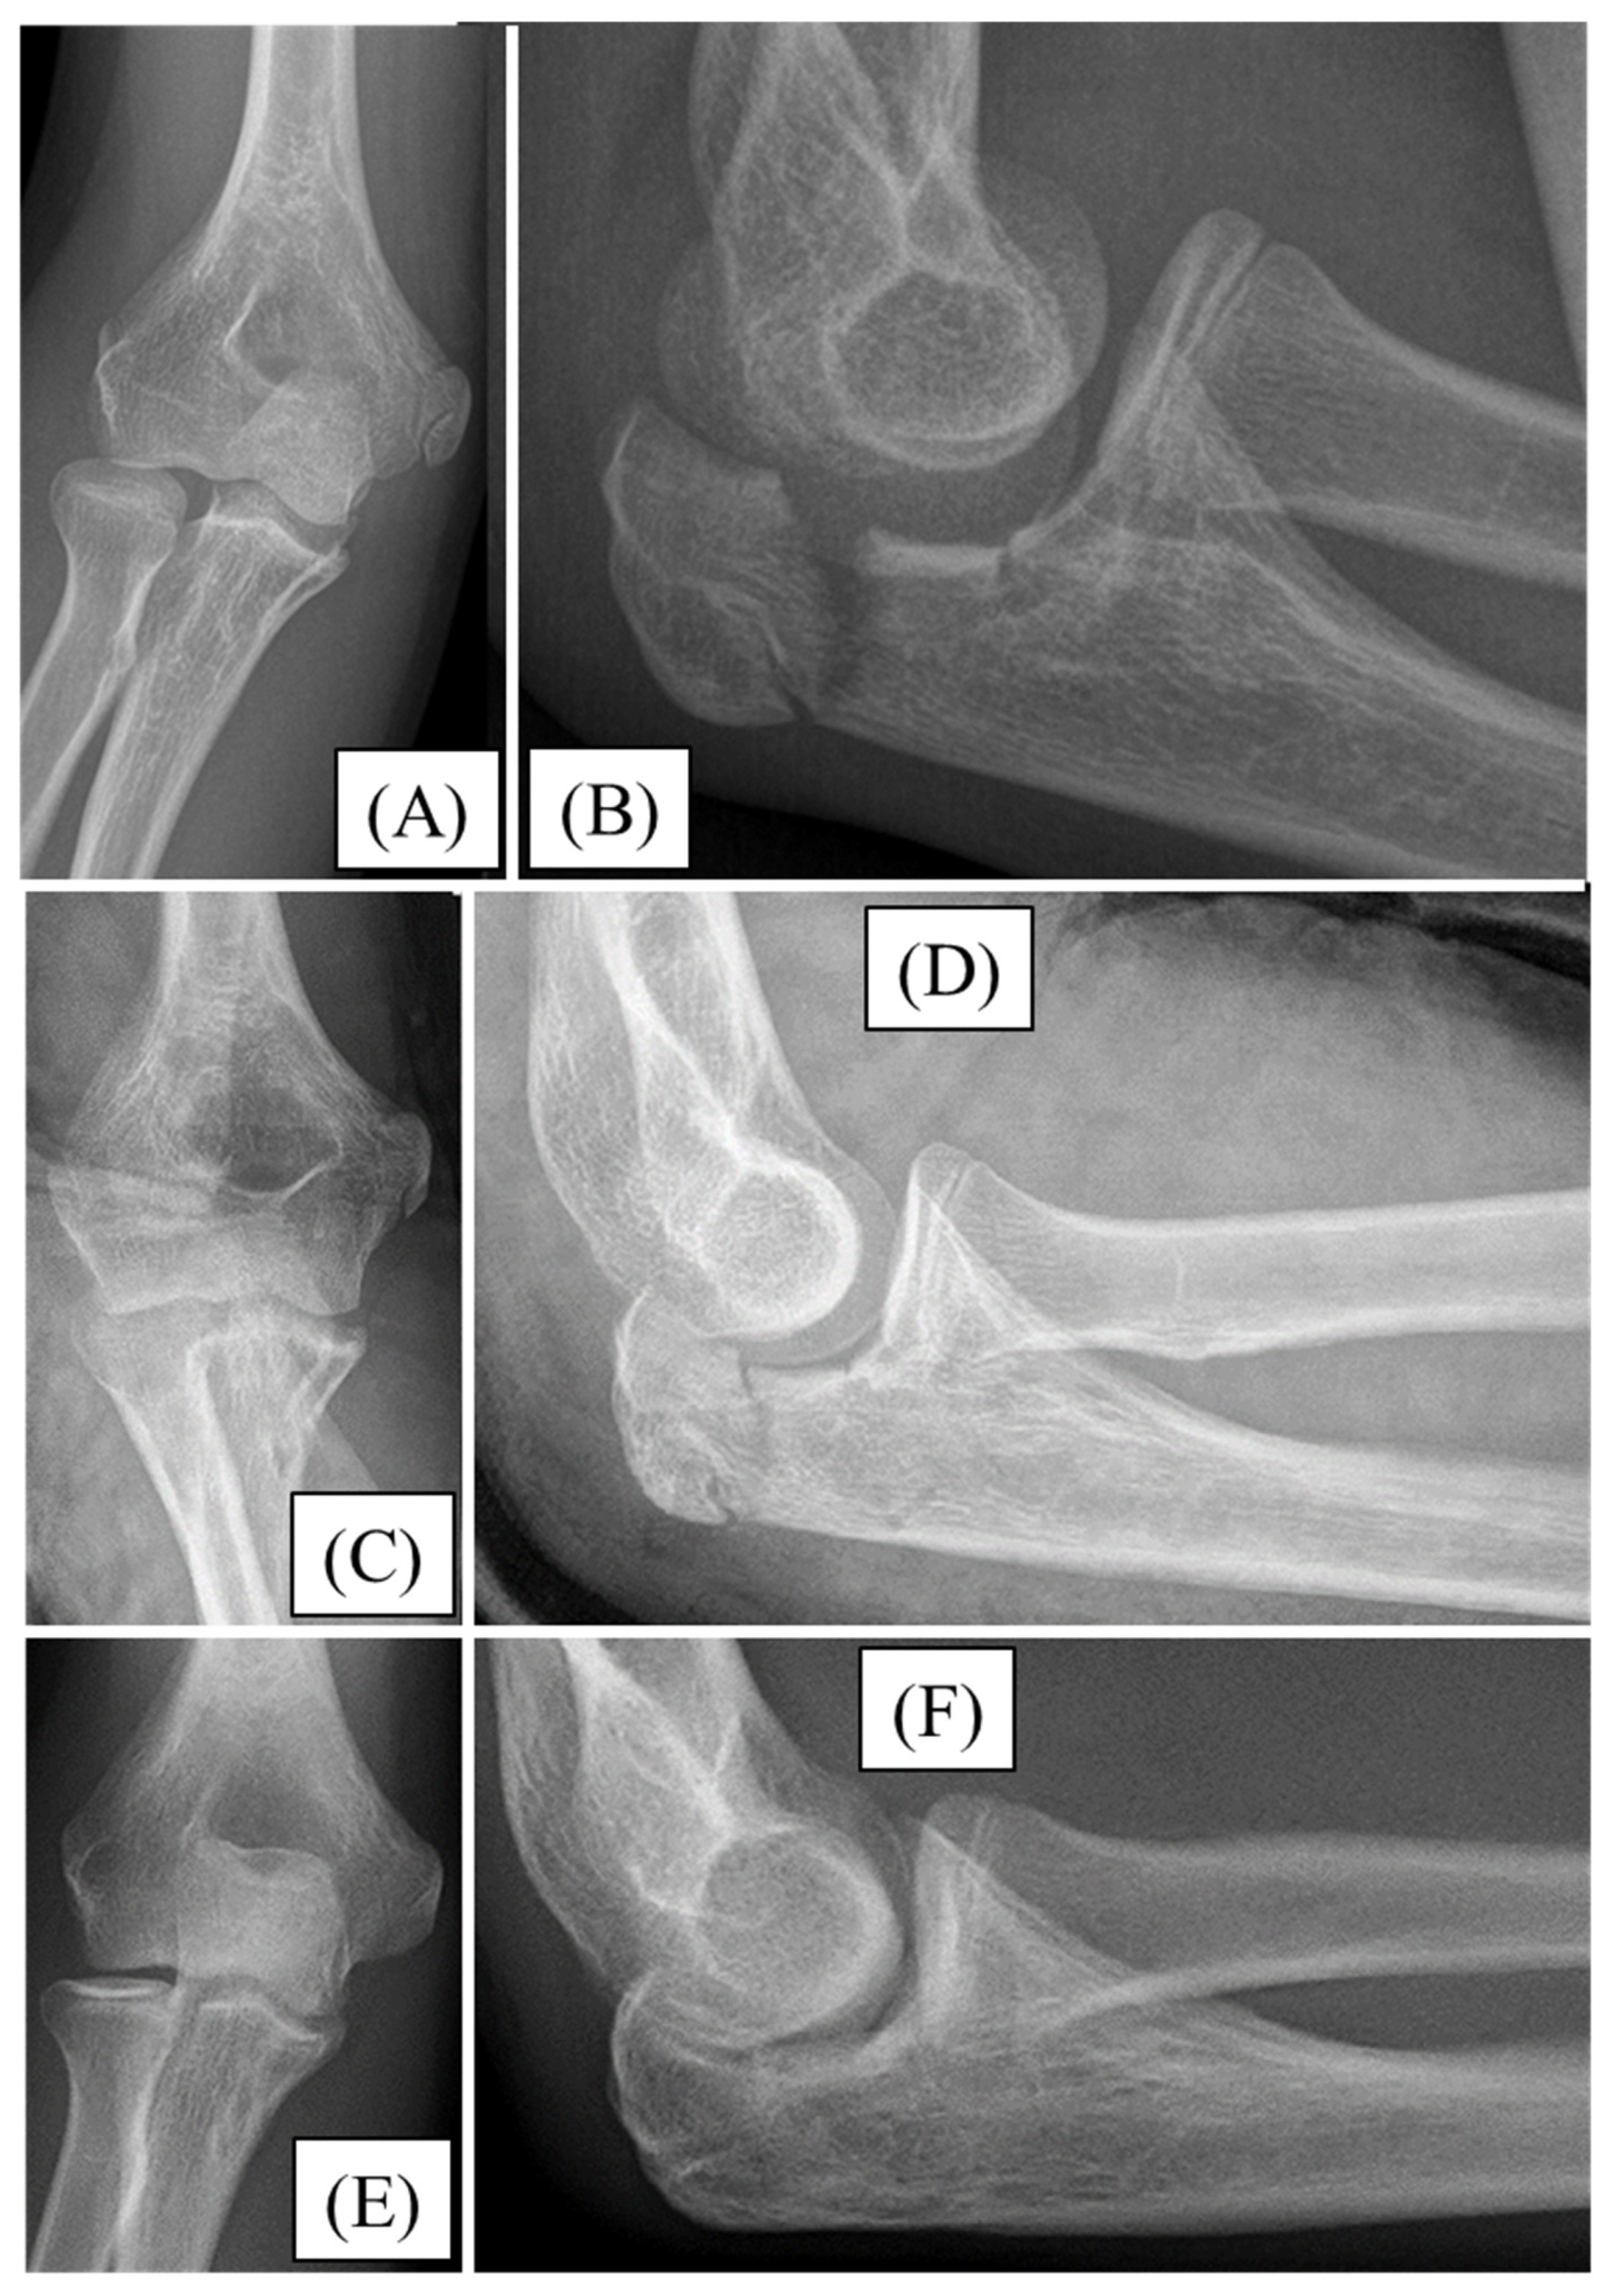

3.3. Case 3